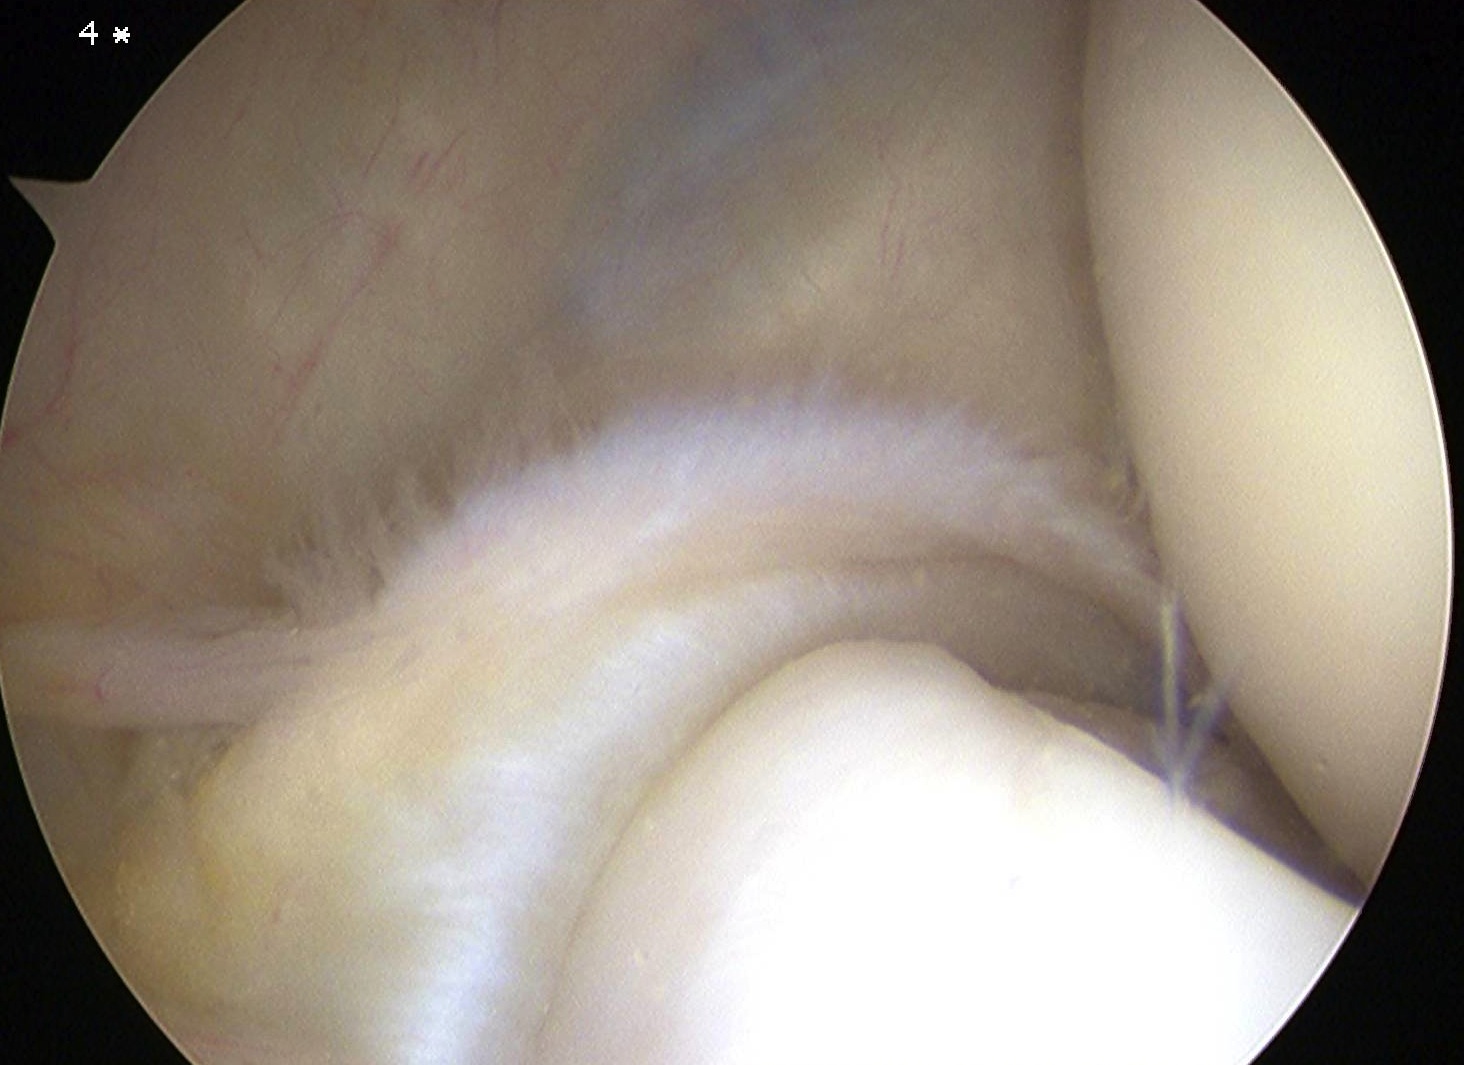

Arthroscopic tennis elbow release

Technique

Enter radiocapitellar joint

- release capsule

- release ECRB